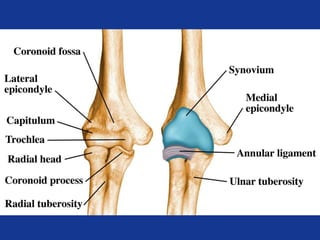

Elbow Anatomy

• Elbow joint is made of

– 3 bones

– 3 joints

– One capsule

– Hinge joint

Lateral epicondyle

Capitulum

Proximal radioulnar

jt.

Radial head

Radial neck

Radial tuberosity

Olecranon fossa

Medial

epicondyle

Trochlea

Coronoid

process

Coronoid Process

Condyles

Trochlear notch

Olecranon

Radial notch